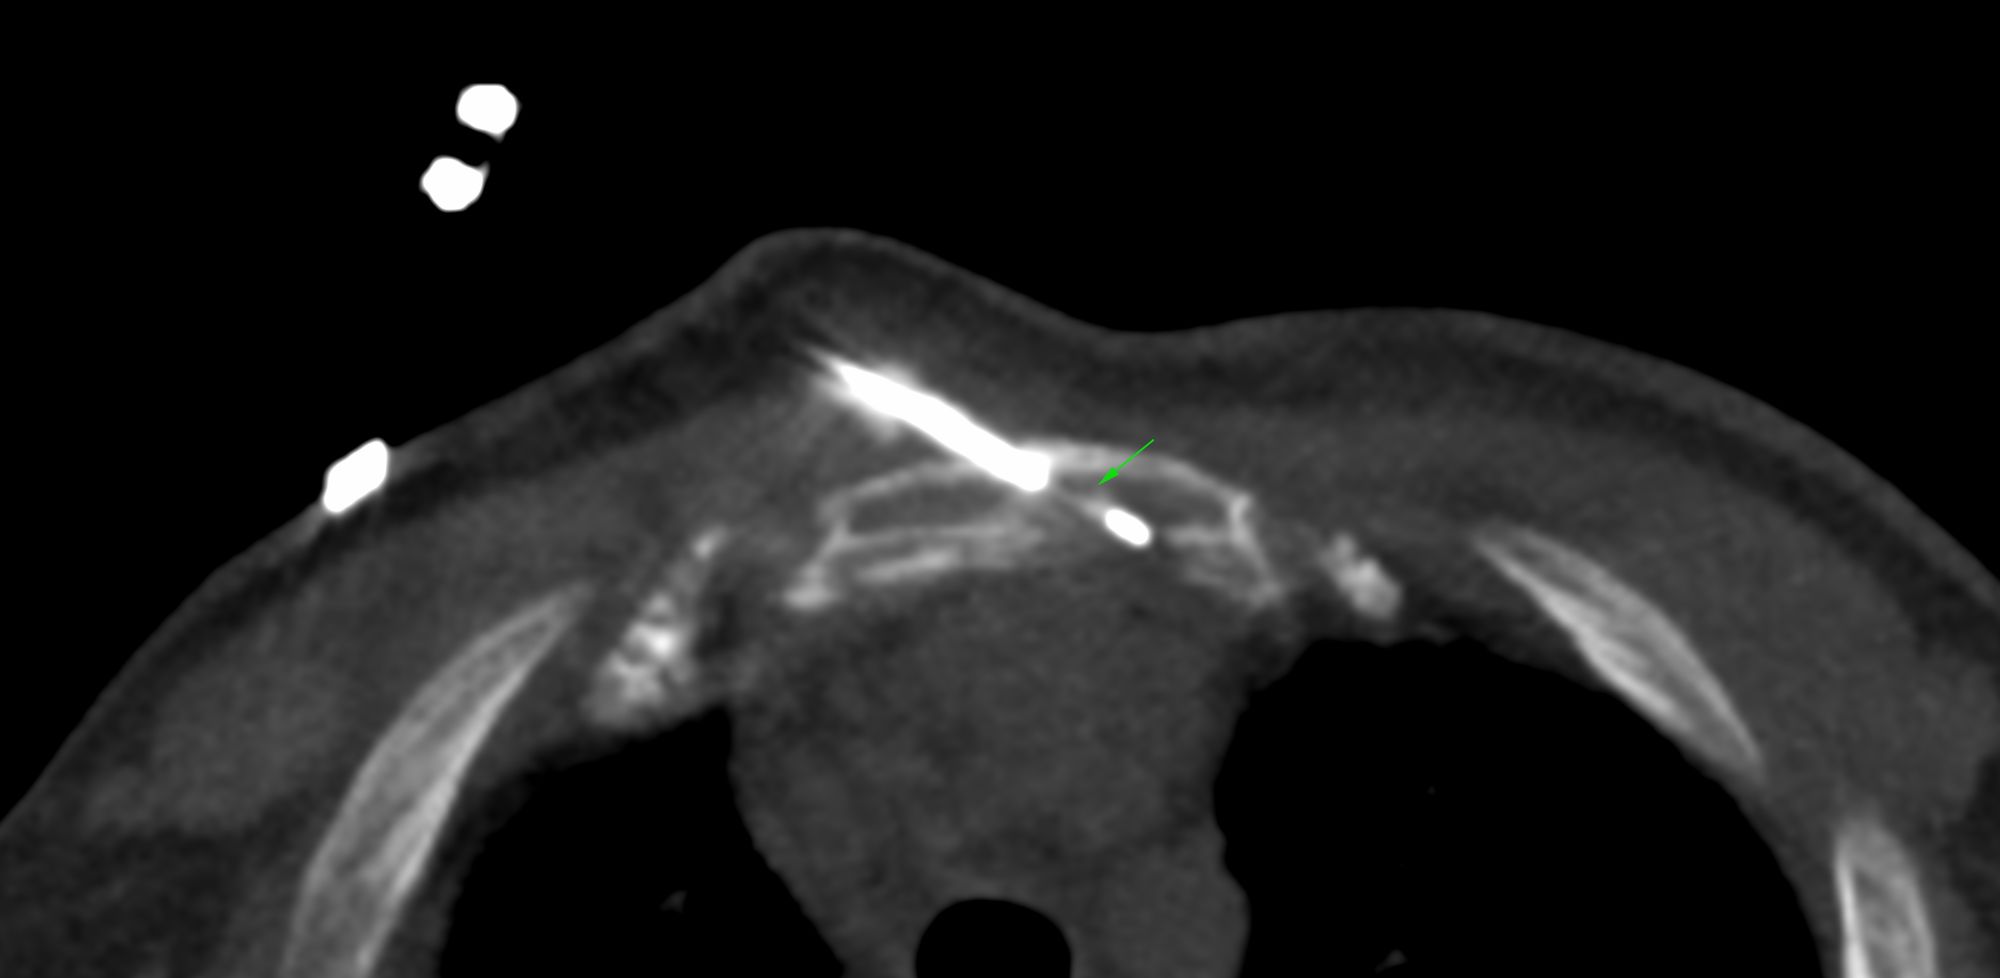

Case 13: Left Mixed Osteolytic-Osteosclerotic Glenoid Bone Lesion Biopsy